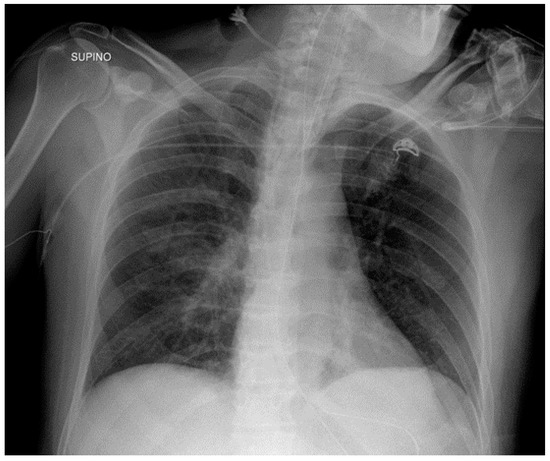

8.2. Vagal Nerve Stimulator (VNS)

8.3. Other Devices